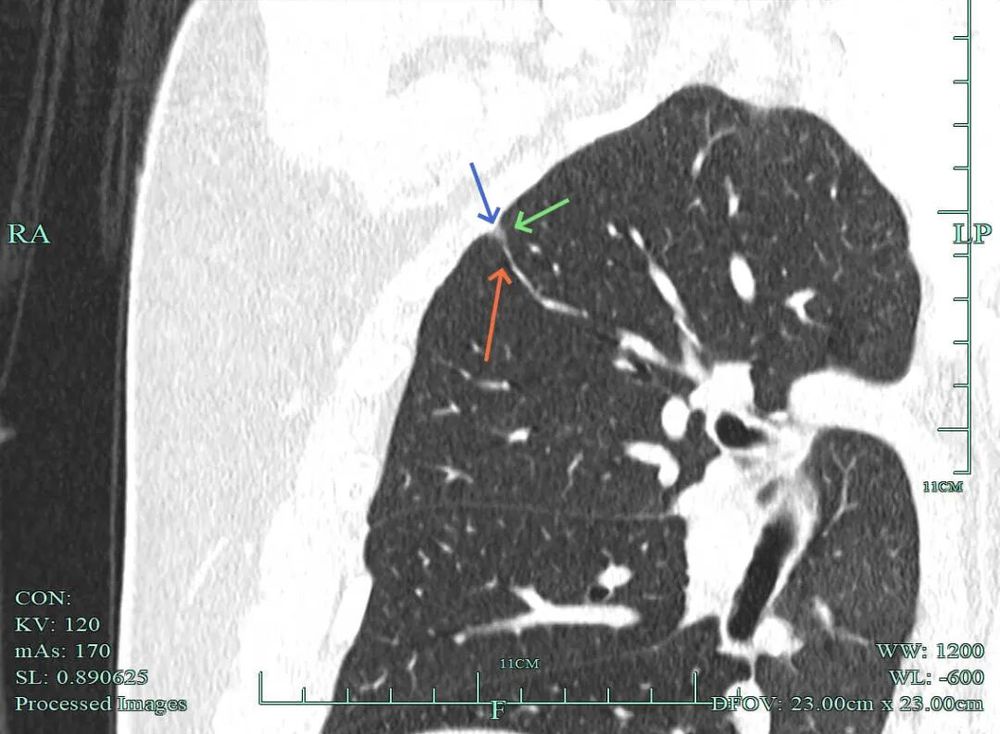

影像展示与分析:

杭州市肿瘤医院影像展示与分析:

右上也有混合密度结节,实性部分缺乏膨胀性与收缩力,磨玻璃成分较淡,也偏糊,但持续存在仍得考虑肿瘤范畴可能性大。

此视角是混合密度,实性为主,贴胸膜近。

左侧主病灶长达三年半时间的随访,当时就是混合密度,整体轮廓较清,随访不好转的话就是要高度警惕恶性的。现在病灶已经明显进展,实性成分增多明显,考虑浸润性腺癌可能性大。肺的粘膜相关B细胞淋巴瘤一般缺乏毛刺征,整体病灶的轮廓与边界会再偏模糊点。但从三年多随访范围增大不多,仍有磨玻璃成分来讲,个人认为已经有转移了的概率可能并高。大概率是中分化浸润性癌可能性大些。右侧病灶也是要考虑浸润性腺癌的,但一是它小些,二是处理要先处理风险更大的一侧,所以右侧病灶拟后续随访叶视其进展再微创干预。

今天这位结友的病理类型稍差于术前的预测,但从其三年多随访情况来看,进展不算大厉害,第10组与第12组淋巴结均阴性的话,还是真早期的可能性还是较大的。后续倾向暂随访观察,可以采取相对稍积极的随访策略,比如两年内4个月复查一次,三到五年内半年复查一次,五年后再年度复查;而且右侧的病灶要在随访进展或身体恢复良好后微创局部楔形切除。期间万一有转移,其实是伪早期的话,则基因检测并全身性治疗。其实今天这种病灶在临床中被判断为炎性的并不少见,尤其是非胸外科医生。因为胸外科的一般相对积极,警惕性高些。在我的公众号上其实也分享过多例这种看着似乎是炎性,但长时间随访不好转,或缓慢进展的病灶其实是浸润性腺癌的一种特殊表现,不少见的。我感觉此类病灶比较主要的临床特征是:1、密度多是混合磨玻璃密度,实性成分较明显,磨玻璃成分较淡,病灶显得密度较为杂乱不均;2、整体形态膨胀性不明显,收缩力不太强;3、灶内支气管通气及显得较为僵硬,血管征不典型,但表面多是不平不规则,较为毛糙,分叶多可见;4、随访或抗炎治疗不好转,进展不快,相对较为缓慢。容易被人以为是慢性炎症。但此时我们要注意几点:1、寻找磨玻璃成分,并观察瘤肺边界,尤其是磨玻璃成分与周围正常肺组织之间的界限是否清楚,清楚的多是恶性;2、靶重建从不同角度观察病灶形态,看病灶与邻近结构的关系,有无推压、破坏或支气管截断等征象;3观察病灶内部通气支气管的形态,扭曲、僵硬不舒展的多容易是恶性病变。总体上,要对“影像看着像慢性炎,但随访持续存在且有磨玻璃成分的”病灶要特别提高警惕,对于靠近边缘部分的,手术创伤不大的,要考虑“开刀带来创伤与随访导致的风险”之间的利弊权衡。我的根本理念仍是:淡化最后病理结果,从风险角度考虑问题!